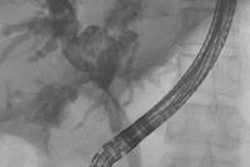

Y-90 radioembolization is an intra-arterial transcatheter therapy in which an interventional radiologist inserts a catheter into the artery in the groin and guides it to the hepatic artery.

Y-90 microbeads are then administered into the bloodstream; these microbeads travel to the smaller vessels that feed the tumor and deliver radiation. Because Y-90 directly targets the tumor, radiation damage to healthy surrounding tissues is minimized.